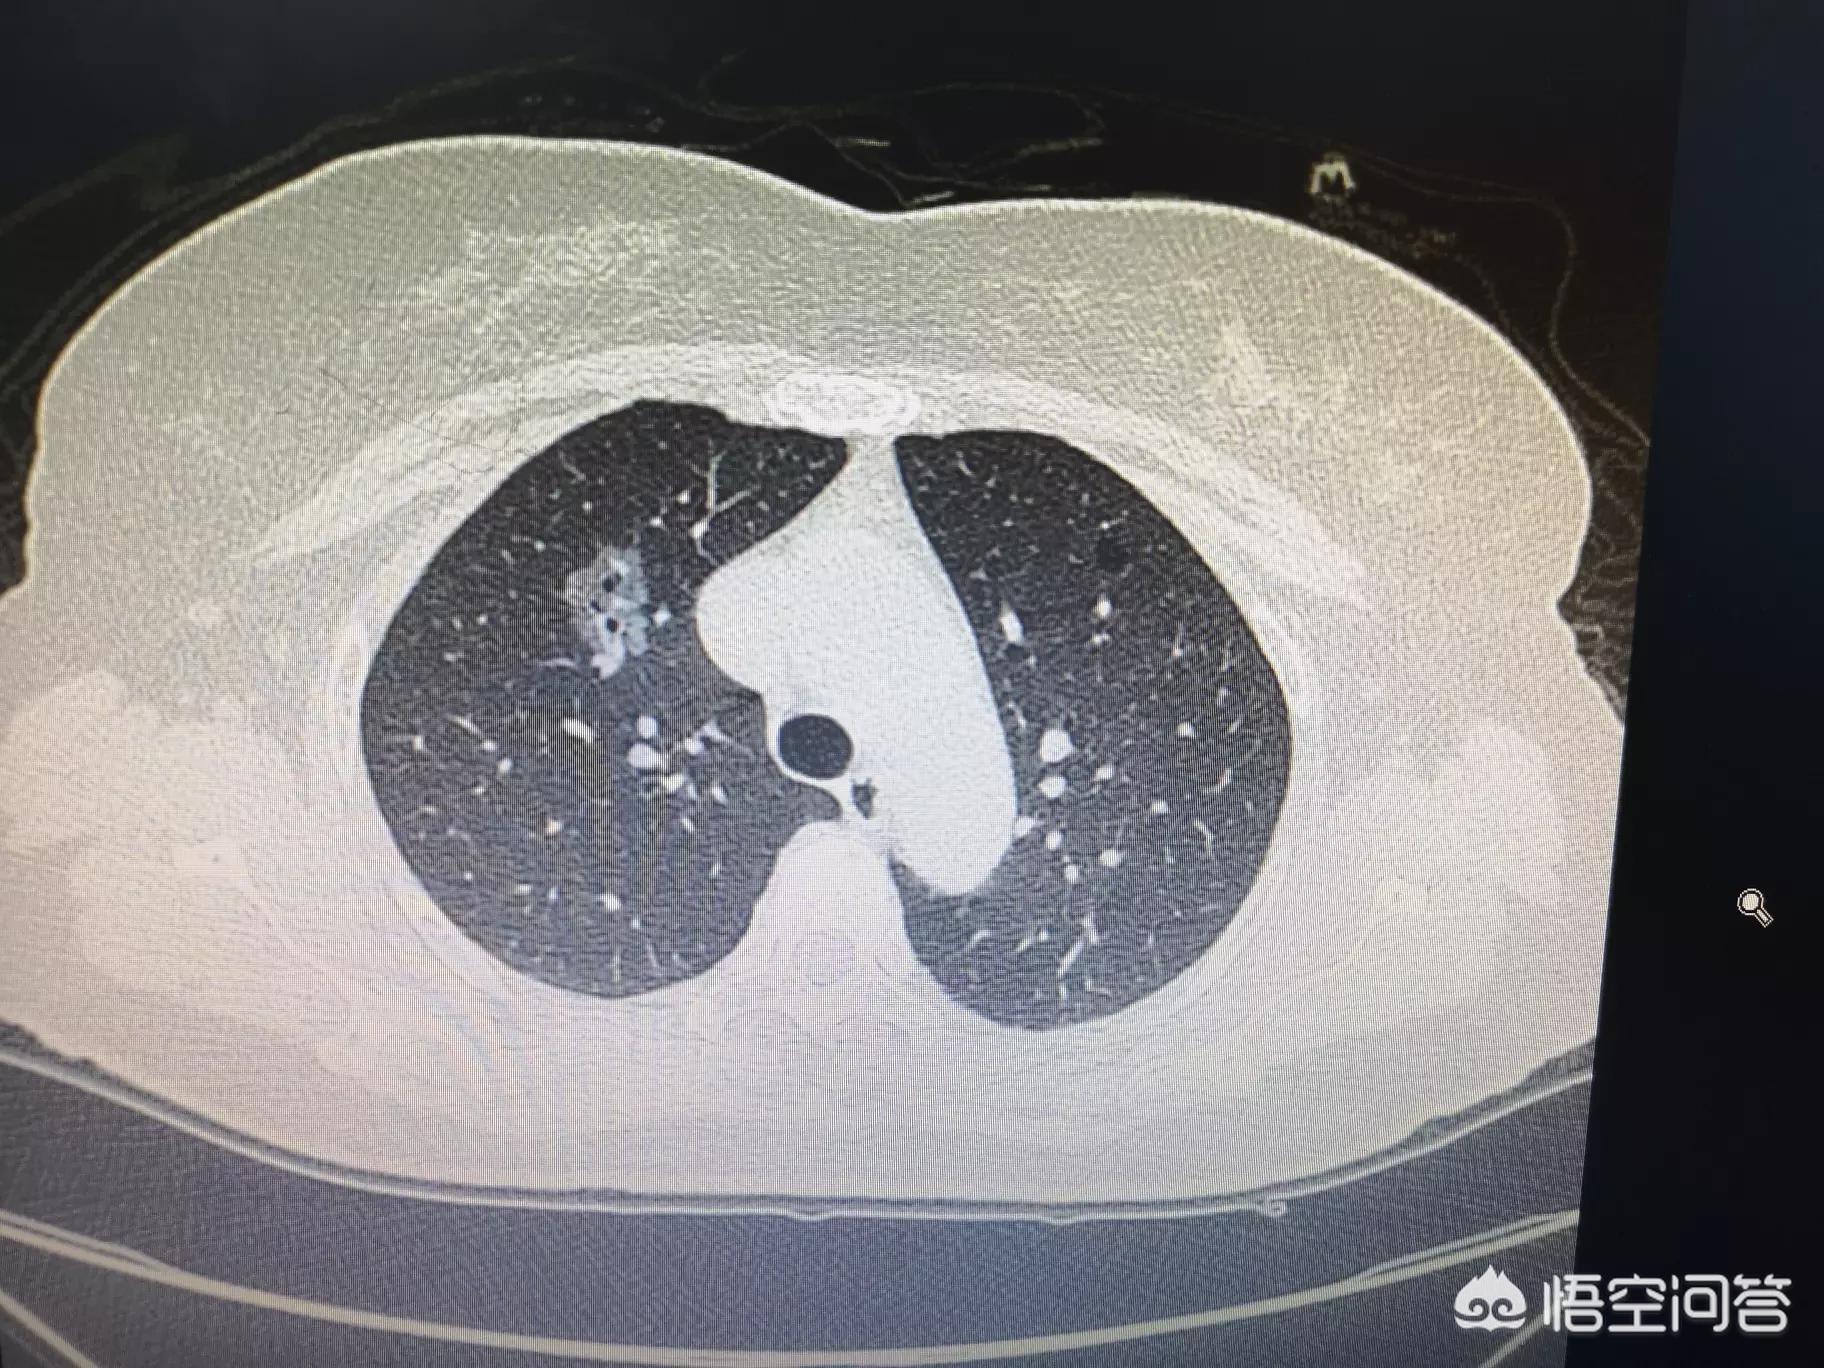

因此,可以这样说,长期在厨房的中老年女性,属于高危人群。要及时进行低剂量螺旋CT进行体检,早发现,早干预。